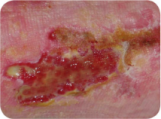

Granulating Wound

Phase of healing without proliferation, high vascular due to the formation of new blood vessels, red in colour.